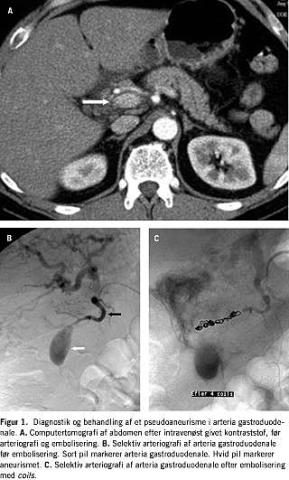

Patienten var en mand født i 1950 og siden april 2001 kendt med alkoholinduceret kronisk pankreatitis. Patientens pan-kreatitis blev kompliceret af dannelse af en pseudocyste ved pancreas, som blev tømt ultralydvejledt tre gange i 2001. Primo januar 2002 havde patienten en et døgn varende episode med melæna og blodtransfusionsbehov. En gastroduodenoskopi viste gastritis og duodenitis, og patienten blev sat i behandling med en protonpumpehæmmer. To uger senere fik han pludselig stærke smerter i den øvre del af abdomen med udstråling til ryggen og op i brystet. Smerterne var væsentligt værre end hans sædvanlige smerter. Ved en objektiv undersøgelse var patienten udtalt øm i epigastriet. Biokemiske undersøgelser viste normale forhold, bortset fra en marginal forhøjet S-amylase og c-reaktiv protein. En computertomografi (CT) viste et pseudoaneurisme i arteria gastroduodenale. Pseudoaneurismet var beliggende i en pancreaspseudocyste (Figur 1A ). Der blev foretaget arteriografi, som viste et 2×3 cm stort pseudoaneurisme i arteria gastroduodenale (Figur 1B). Herefter blev der foretaget superselektiv arteriografi af arteria gastroduodenale, og arterien blev endovaskulært emboliseret med coils både proksimalt og distalt for pseudoaneurismet (Figur 1C). Patientens smerter aftog betydeligt efter emboliseringen, og han blev udskrevet tre dage senere. En kontrol-CT efter en måned viste ingen tegn på recidiv af pseudoaneurismet. Patienten var velbefindende 26 måneder efter behandlingen.